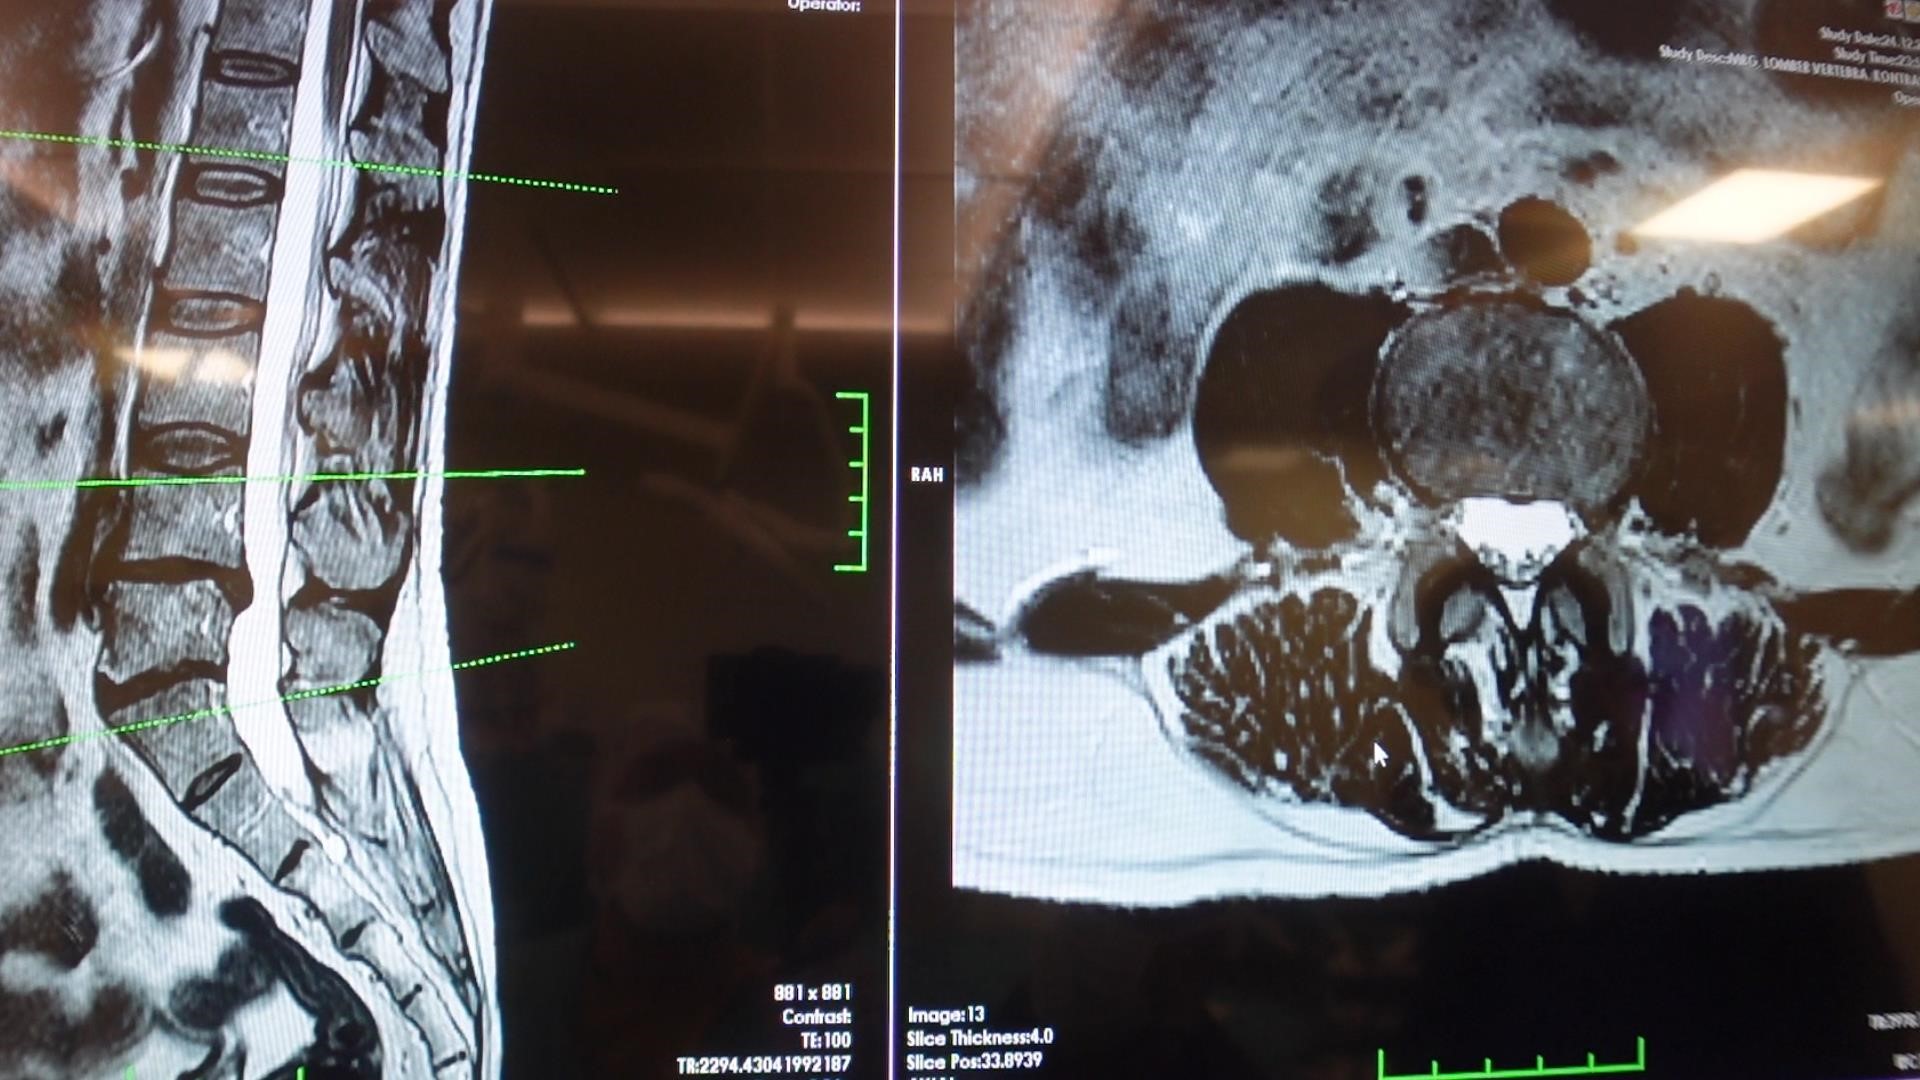

Prof. Dr. Erol ayrıca omurilik kanal darlığına da dikkat çekti. Dejeneratif süreçler nedeniyle omurilik kanalında ve sinir köklerinin geçtiği alanlarda daralma ve kireçlenme oluşabildiğini belirten Erol, bu durumun sinir sıkışmasına yol açtığını aktardı. Bu hastaların özellikle ayakta dururken ya da yürürken bel, kalça ve bacaklara yayılan şiddetli ağrılar yaşadığını, yürüyüş mesafesi arttıkça oturup dinlenme ihtiyacı duyduklarını ifade etti.

Tedavinin doğru tanıya göre planlanması gerektiğini vurgulayan Erol, bel ve bacak ağrısı yaşayan kişilerin mutlaka bir beyin ve sinir cerrahisi uzmanına başvurması gerektiğini belirtti. Yapılacak muayene ve tetkiklerle hastalıkların birbirinden ayrılabildiğini ve buna göre uygun tedavi planının oluşturulduğunu sözlerine ekledi.